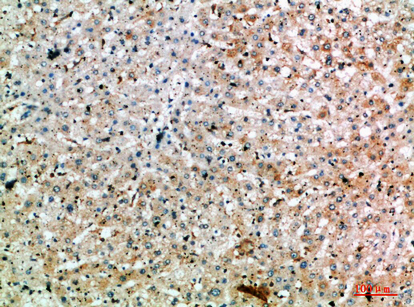

分类: 科研抗体货号: P43463别名: UBC16; UBC-16应用: WB,IHC反应种属: Human,Rat